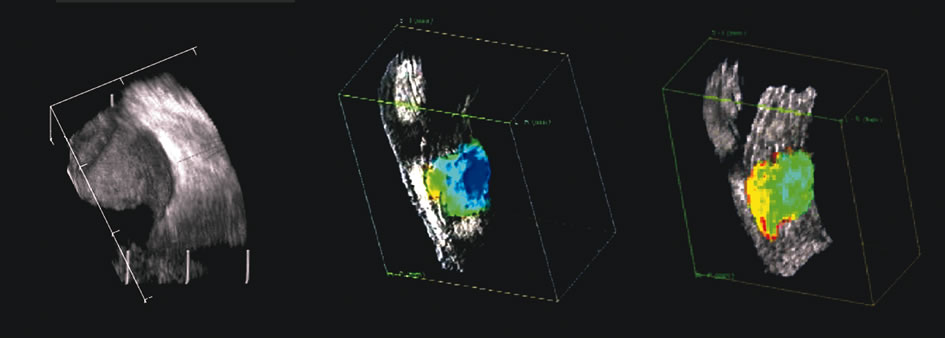

of the posterior segment. Retina 18:251, 1998 42. Atta HR: New applications in ultrasound technology. Br J Ophthalmol 83:1246, 1999 43. Basset O, Gimenez G, Mestas JL, et al: Volume measurement by ultrasonic traverse or sagittal cross-sectional

scanning. Ultrasound Med Biol 17:291, 1991 44. Kidd MN, Lyness RW, Patterson CC, et al: Prognostic factors in malignant melanoma of the choroid: A retrospective

features as a predictor of death. Am J Ophthalmol 110:380, 1990 48. Silverman RH, Folberg R, Boldt HC, et al: Correlation of ultrasound parameter imaging with microcirculatory patterns

in uveal melanomas. Ultrasound Med Biol 23:573, 1997 |